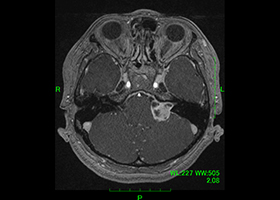

症例1)52歳女性 左聴神経鞘腫、外科治療のみ

[画像所見]

-

術前MRI:右内耳道内に脳腫瘍を認めます。

[手術所見]

内耳孔内の腫瘍摘出 -

顔面神経の温存 -

術前MRI -

術後MRI、腫瘍消失、顔面神経麻痺なし。